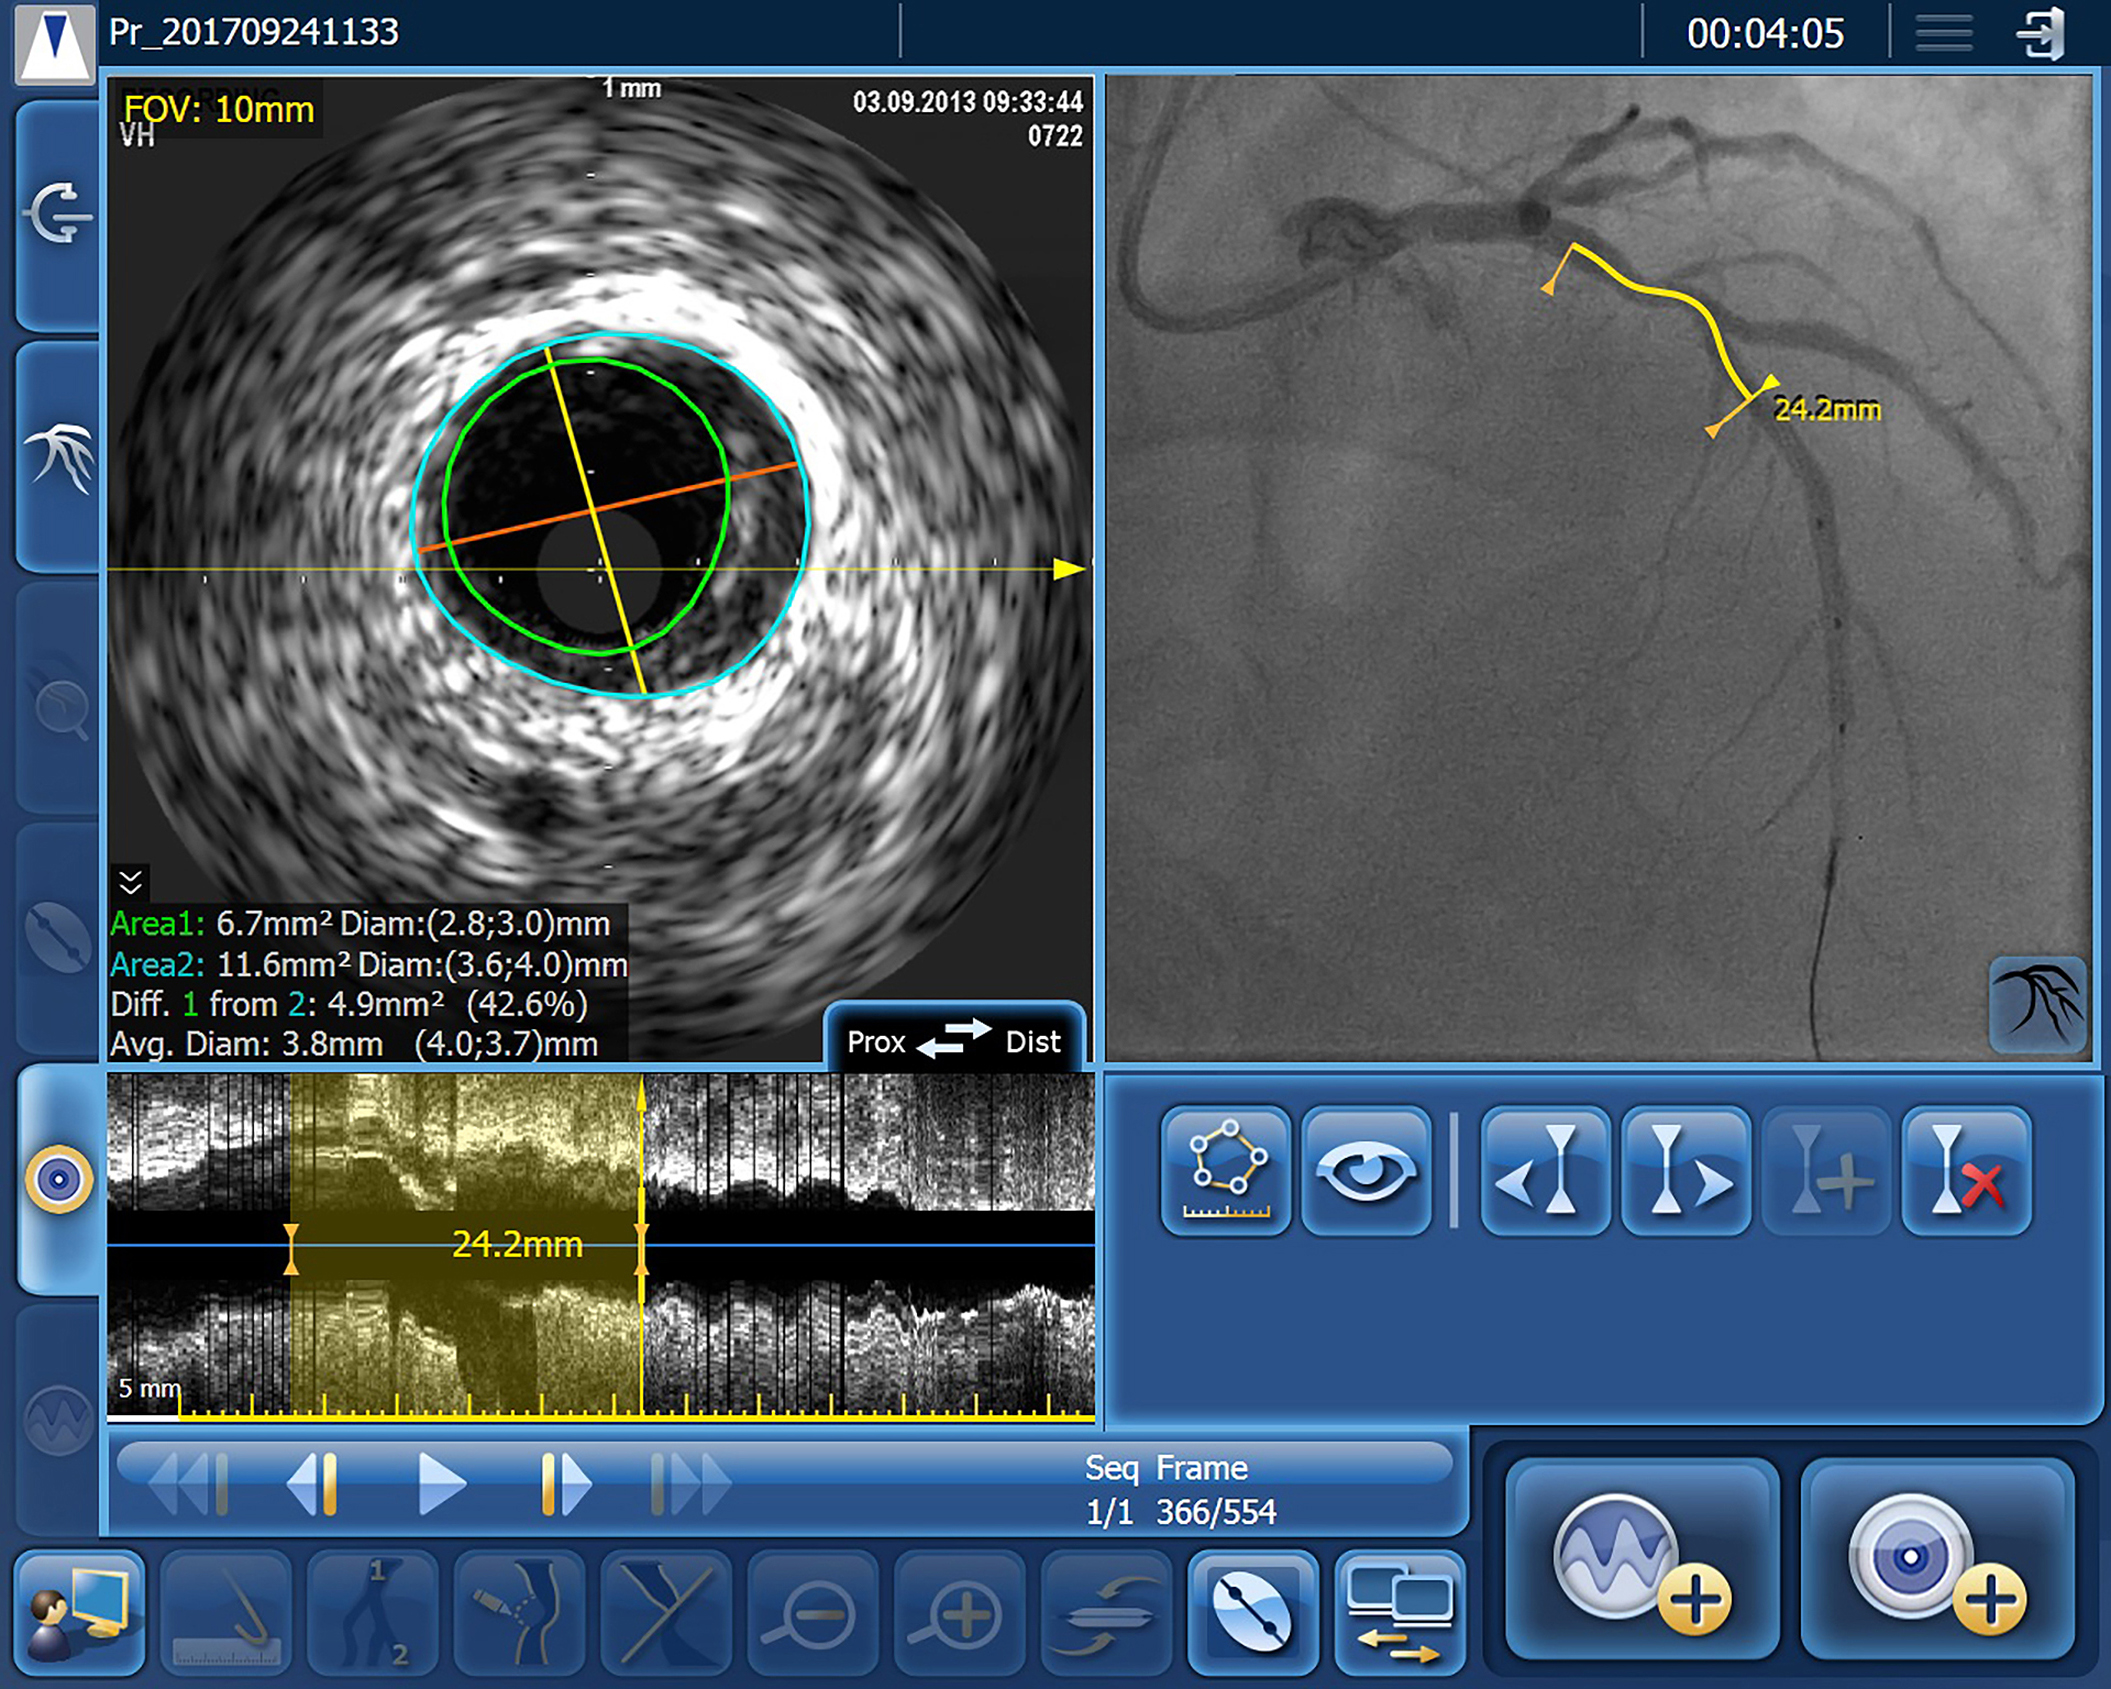

IntraSight Series 7’s IVUS co-registration facility merges real-time intravenous ultrasound and angiogram images, with information on the precise location of the ultrasound images derived during manual pull-back of the ultrasound catheter under continuous fluoroscopy. As a result, interventionists can simultaneously view reconstructed cross-sectional ultrasound images of the vessel lumen, including their precise position on the angiogram. This level of precision significantly reduces the risk of a ‘geographic miss’, which has been estimated to occur in over 60% of PCIs [3]. IntraSight Series 7’s Angio+ quantitative coronary analysis software automatically calculates lumen dimensions and stenosis in real time, helping accurate assessment of the required stent size.